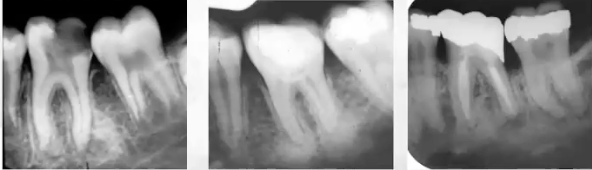

Pano of osteoma

Well circumscribed radiopaque lesion

Radiographic image of osteoma

Pano of patient with gardner syndrome

Pano of patient with Gardner Syndrome has supernumerary teeth

Seen in 20% of patients and cleidocranial dysplasia (more common)